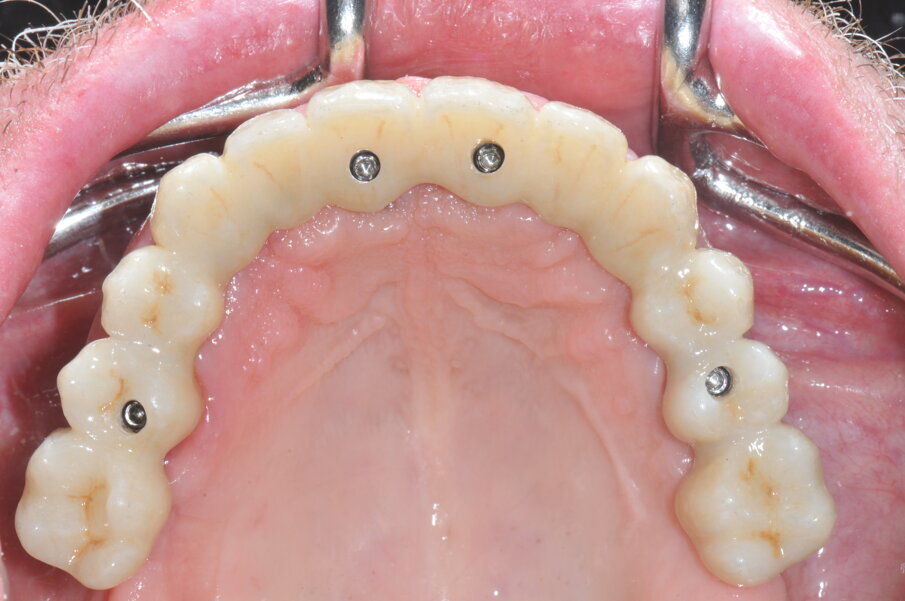

È stata realizzata una riabilitazione full-arch con framework in cromo medicale e rivestimento in ceramica. Il corretto accoppiamento e la passività della struttura protesica sono stati valutati clinicamente e radiograficamente. Le viti protesiche di fissaggio sono state serrate ad un torque di 30N/cm (Figg. 5a, 5b).

Fig. 4a_Visione occlusale degli impianti posizionati tramite dima chirurgica.

Fig. 5b_Visione occlusale della riabilitazione protesica definitiva.